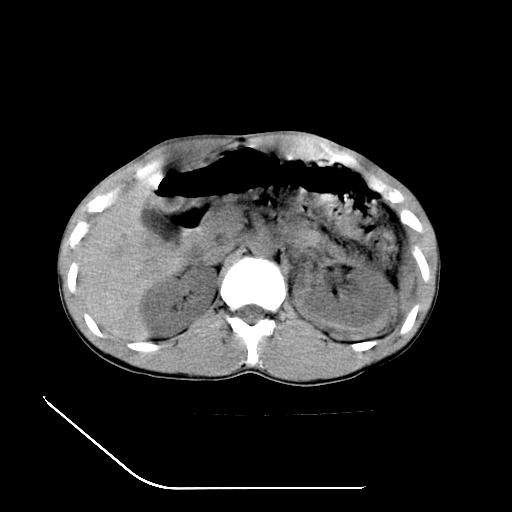

m-25y 高空堕落 12 月5号

12月7号病人尿量200ml/24h 急查双肾ct

左肾挫裂伤并肾周血肿;

肝肾间隙可见液区,建议手术探查;

左肾挫裂伤并肾周血肿

支持 : 左肾挫裂伤并肾周血肿

支持:1、左肾挫裂伤并肾周血肿;

2、少量腹水;

3、左肾旋转不良;

4、反射性肠淤张。

除了1:左肾挫裂伤并肾周血肿;

2:少量腹水

第二次ct检查后:临床医生腹水穿刺后考虑肠系膜动脉破裂,后实行剖腹探查:于空肠距离十二指肠90cm处发现肠管破裂,破裂口较小;修补后关腹。